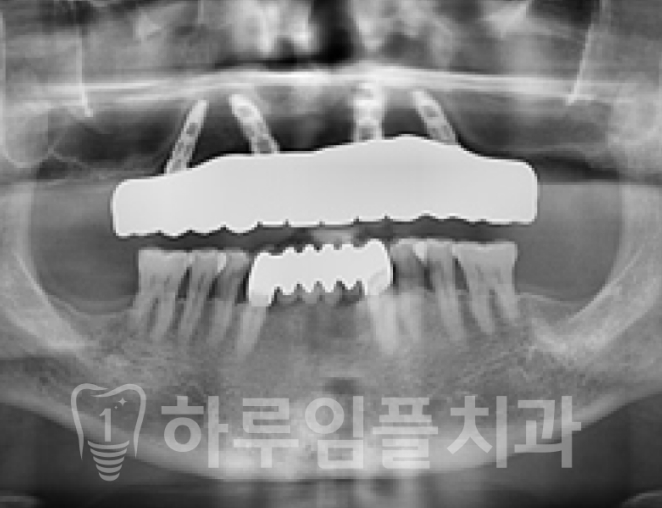

물론, 그 후에는 동일하게 고정성 보철물을

바로 연결해드렸습니다.

최종보철물 까지 체결한 후의 사진입니다.

전체임플란트에 비해 치료과정에서의

신체적, 경제적 부담을 줄일 수 있고

치료기간도 줄어드는 장점이 있습니다.